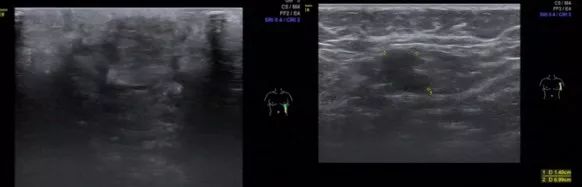

基线影像检查:乳腺MRI(2018年10月31日):左乳下象限肿块,大小6.8cm×4.8cm×6.7cm,BI-RADS:5,左腋窝多发淋巴结转移。乳腺超声(2018年11月5日):左乳肿物,BI-RADS 6;左乳下方象限可见肿物,左侧腋窝可见皮髓质结构消失淋巴结;右乳未及异常。PET-CT(2018年11月1日):左乳癌,左侧腋窝转移淋巴结可能性大。骨(-)、双肺(-)、肝(-)、脑(-)。

乳腺超声(2018年11月5日)

肿块明显缩小,皮肤受侵,但无破溃迹象。乳腺超声(2019年3月4日):左乳癌新辅助化疗后未见明确肿物。乳腺钼钯(2019年3月4日):未见明确肿物。乳腺MRI:左乳下象限肿块较前明显缩小,左腋窝多发淋巴结较前减小。疗效评价部分缓解(partial response,PR)。

乳腺超声(2019年3月4日)